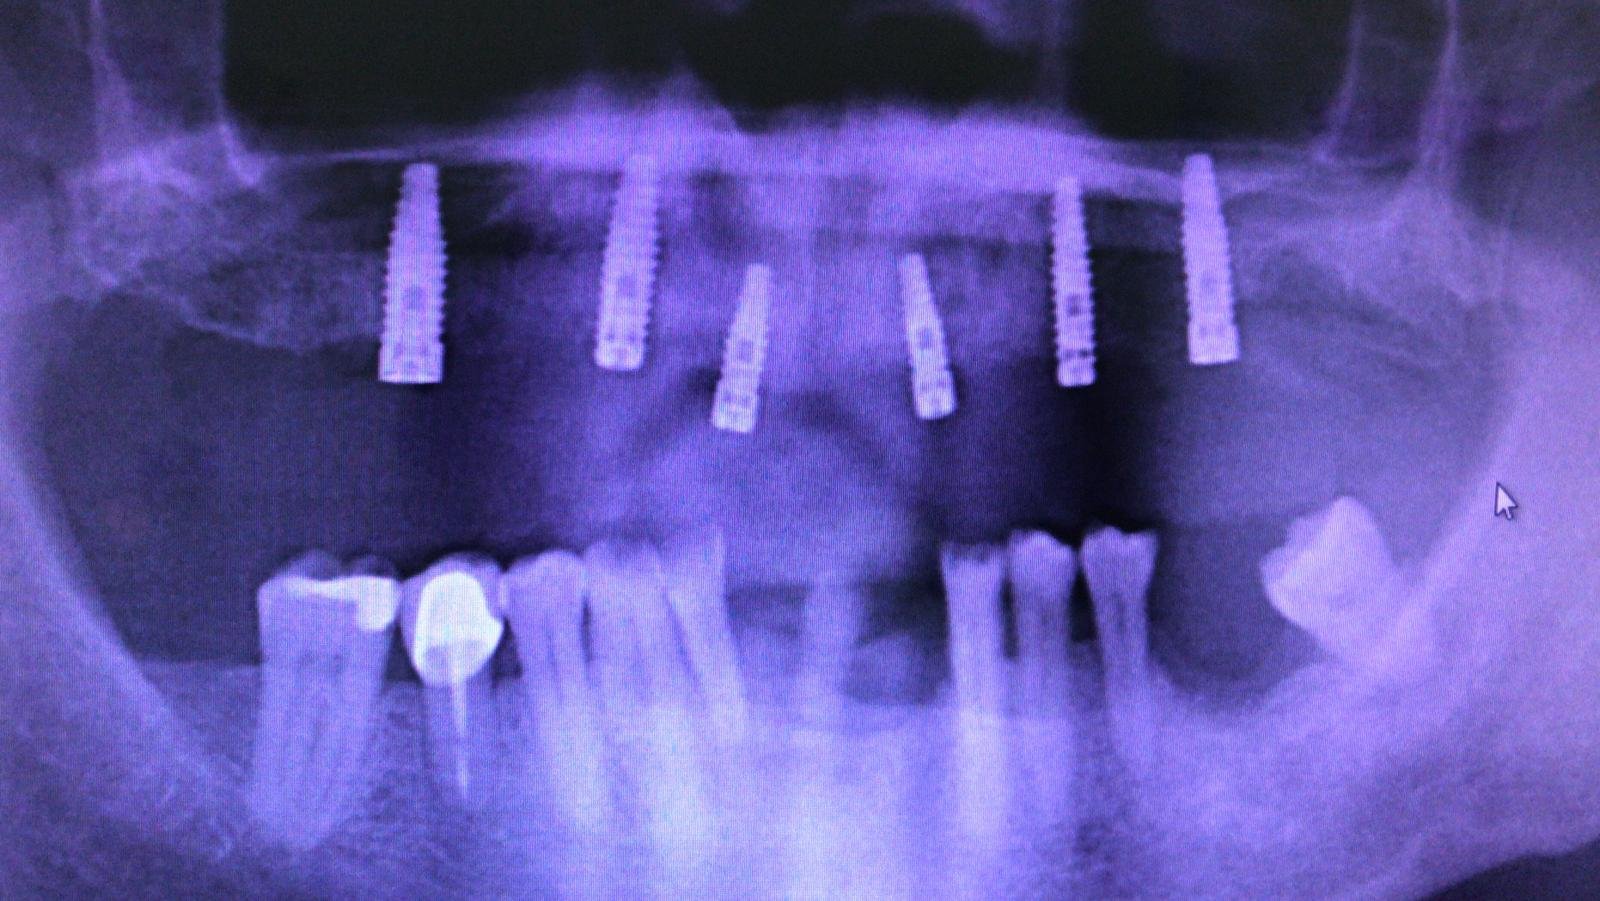

Paciente que tiene que rehabilitarse los implantes y no sabe qué implantes son, me gustaría vuestra ayuda por favor.